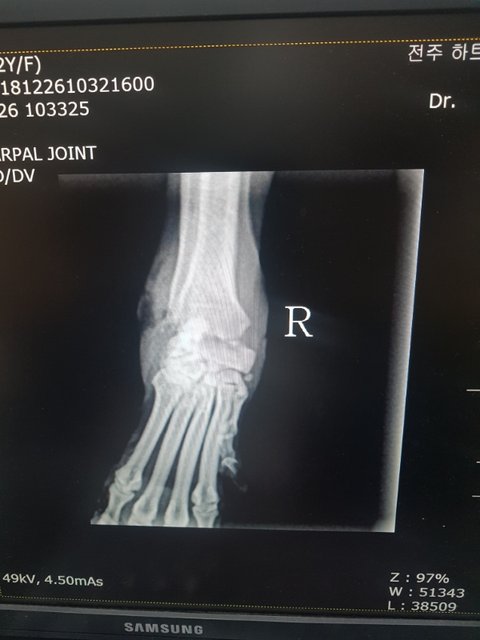

골절...염증이 심해 연골과 뼈일부분이 녹아내리고 있다고 합니다

염증먼저 가라앉히고 수술여부를 결정하신다고 합니다

2살추정 6.5키로 여아입니다